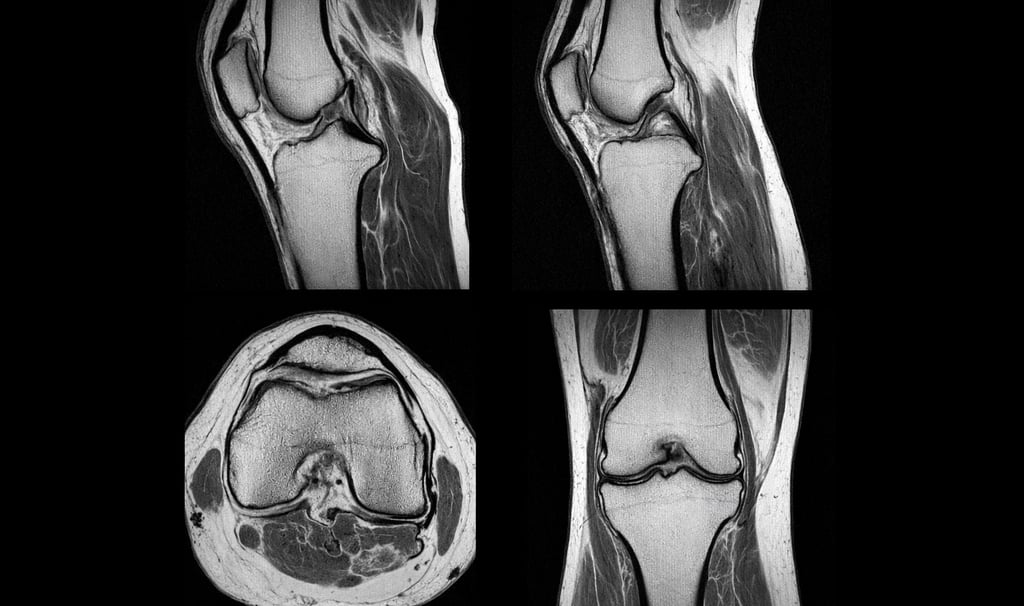

IRM du genou

L’IRM du genou est l’examen de référence pour :

confirmer la lésion

évaluer sa gravité

orienter le traitement

👉 Lire aussi : IRM du genou